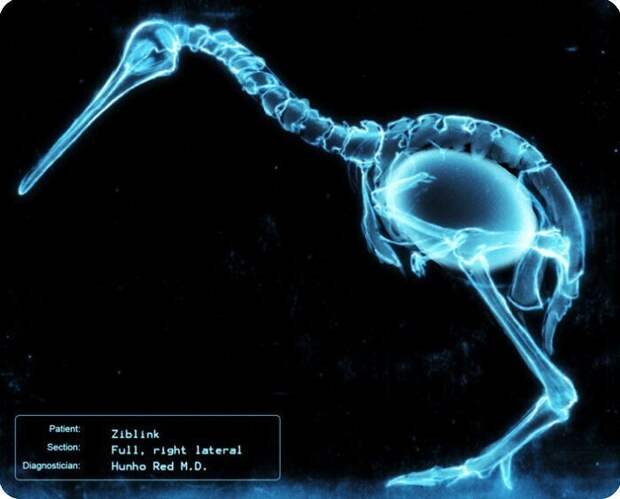

Птица киви готовится снести яйцо